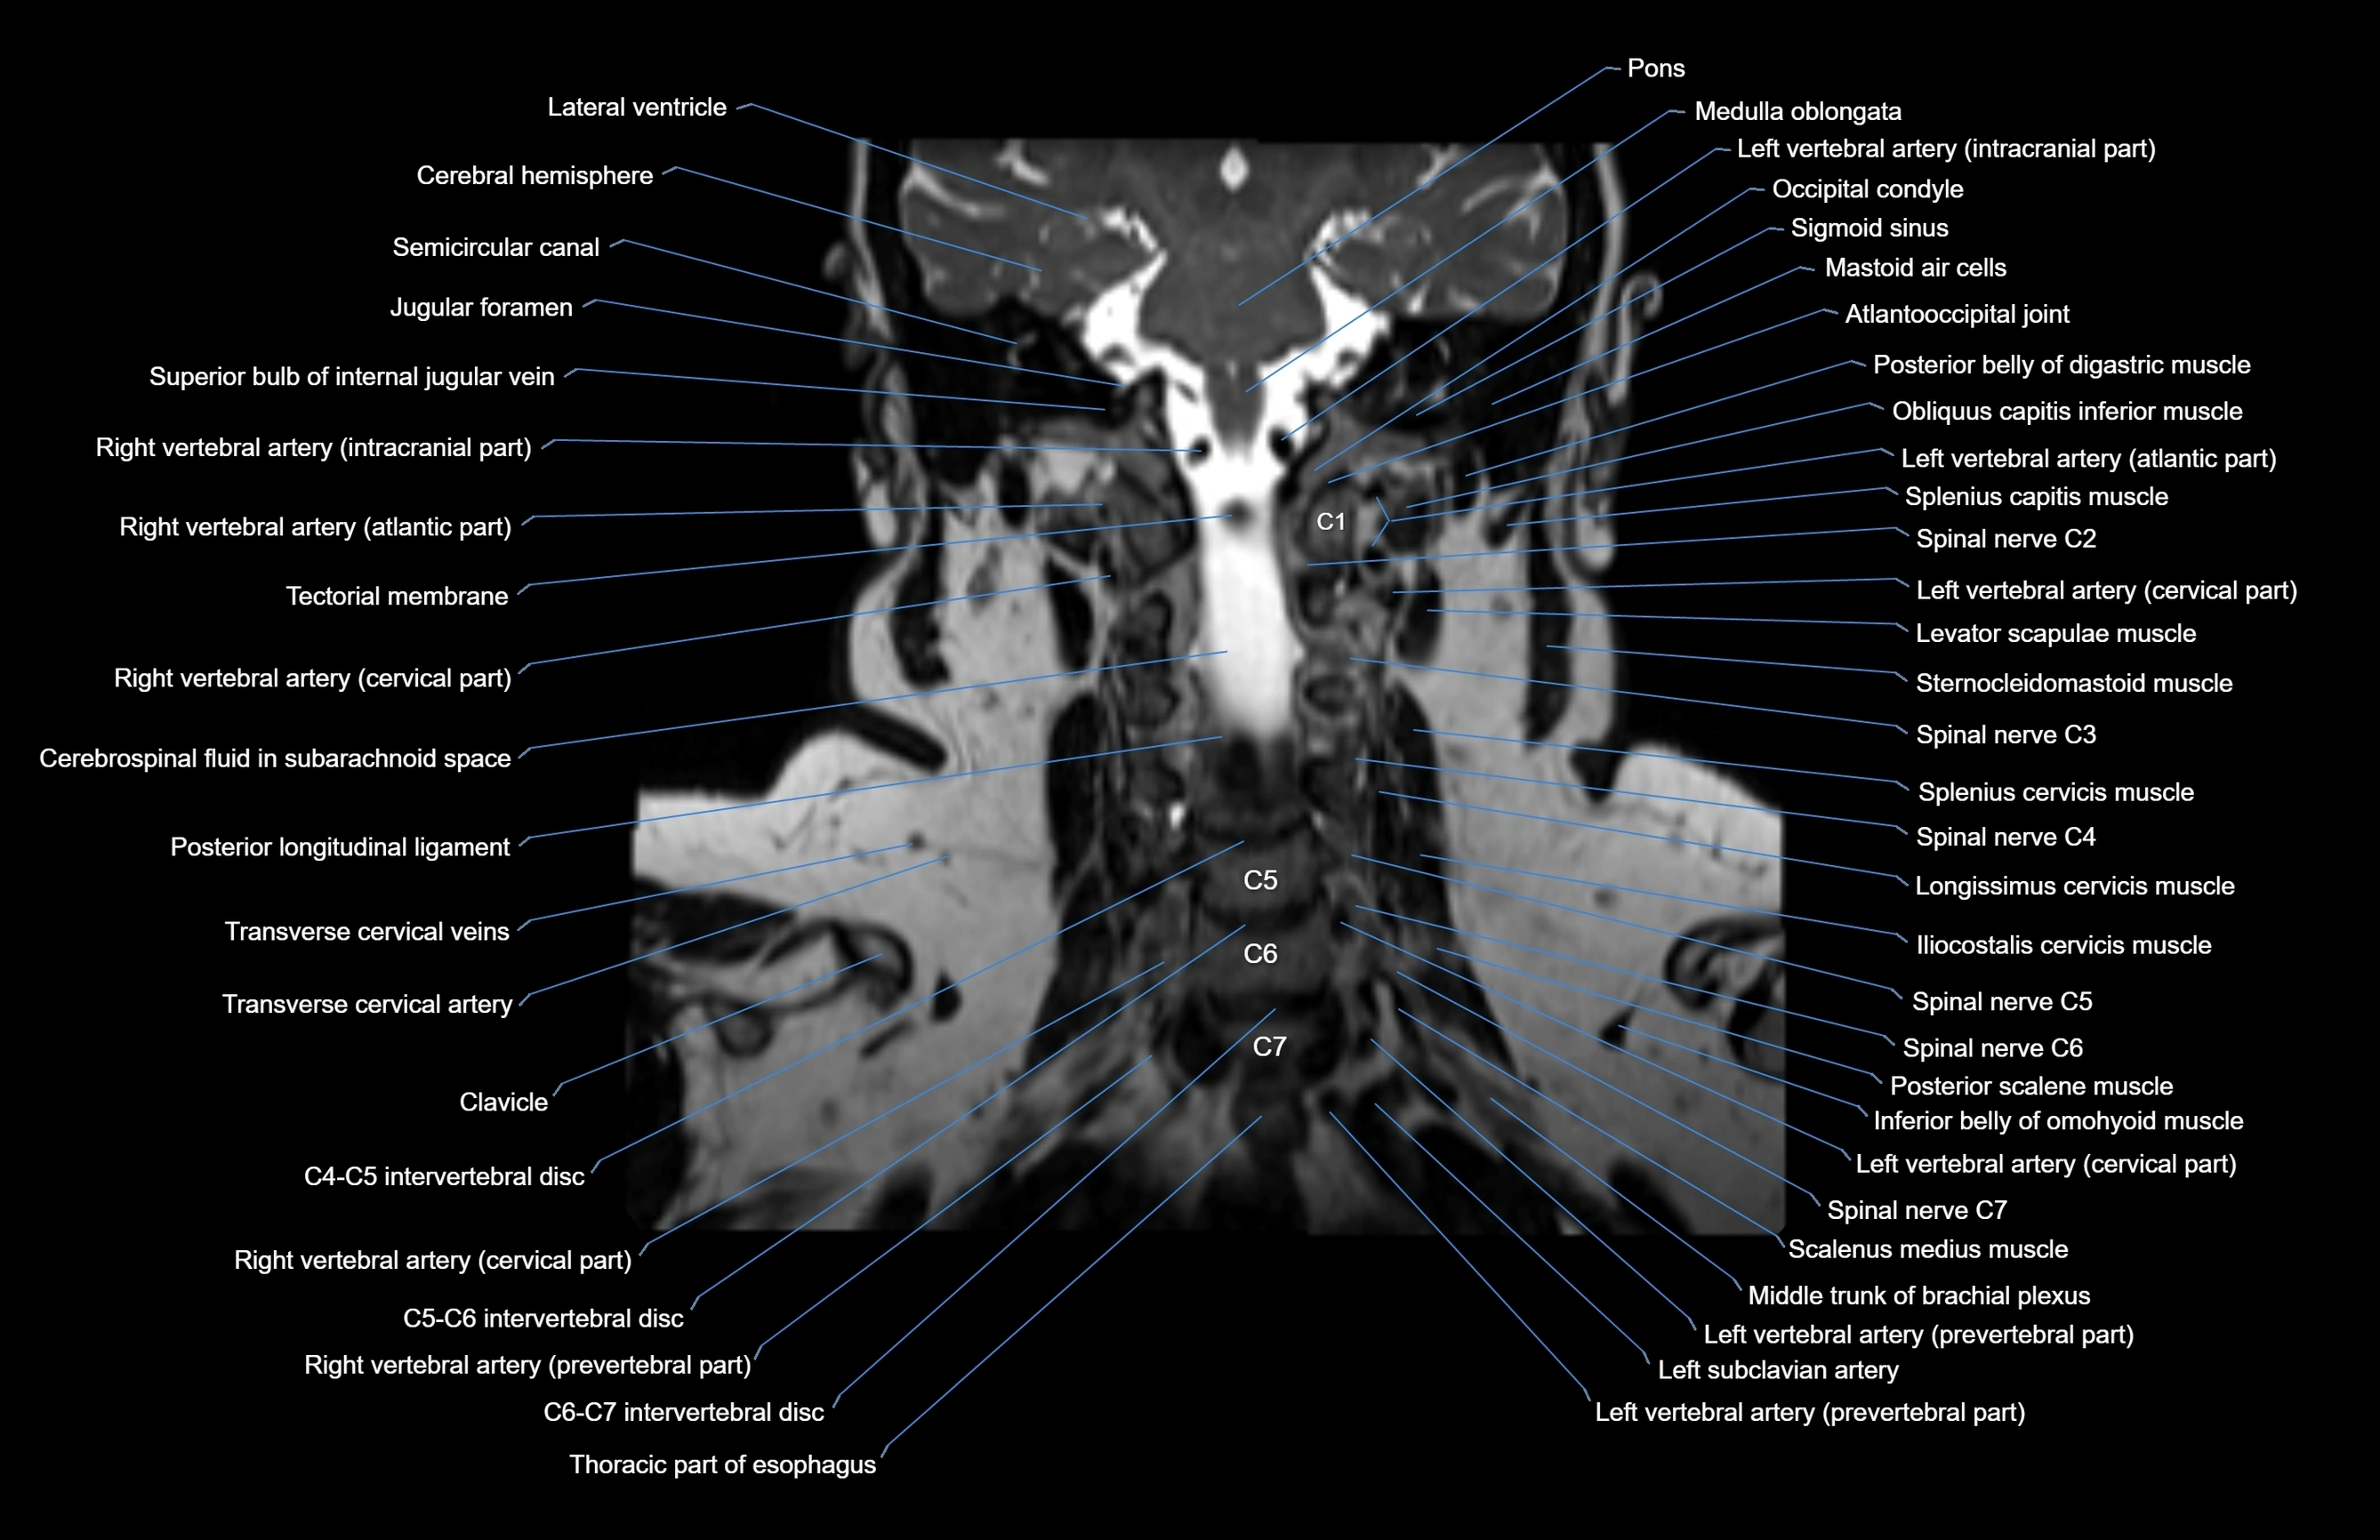

- Atlantooccipital joint

- Cervical spinal nerve 2 (C2)

- Cervical spinal nerve 3 (C3)

- Cervical spinal nerve 4 (C4)

- Cervical spinal nerve 5 (C5)

- Cervical spinal nerve 6 (C6)

- Cervical spinal nerve 7 (C7)

- Left vertebral artery (atlantic part)

- Left vertebral artery (cervical part)

- Right vertebral artery (atlantic part)

- Right vertebral artery (cervical part)